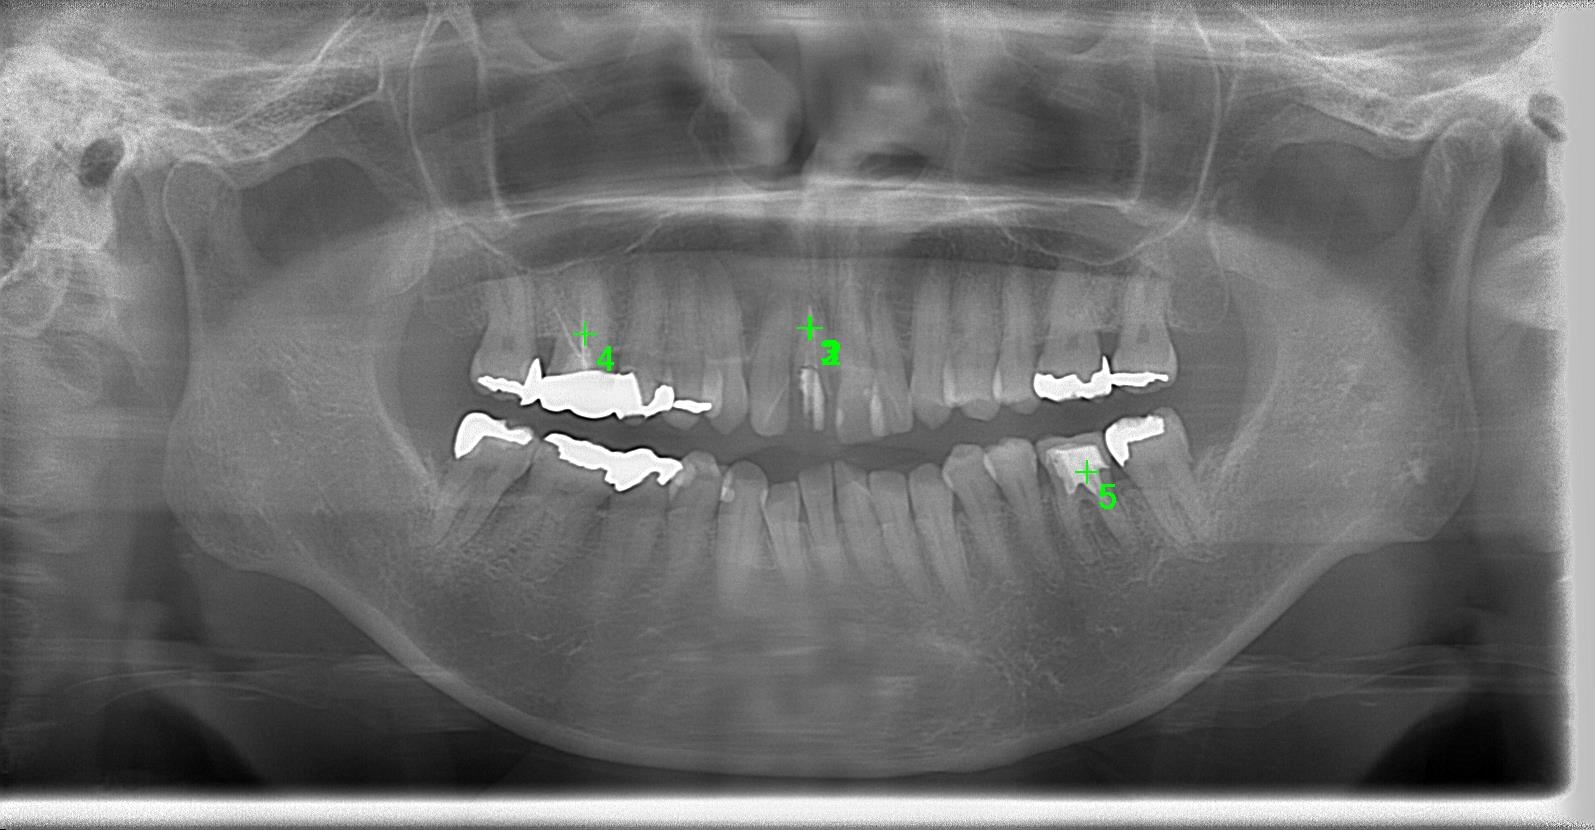

術前パノラマレントゲン写真